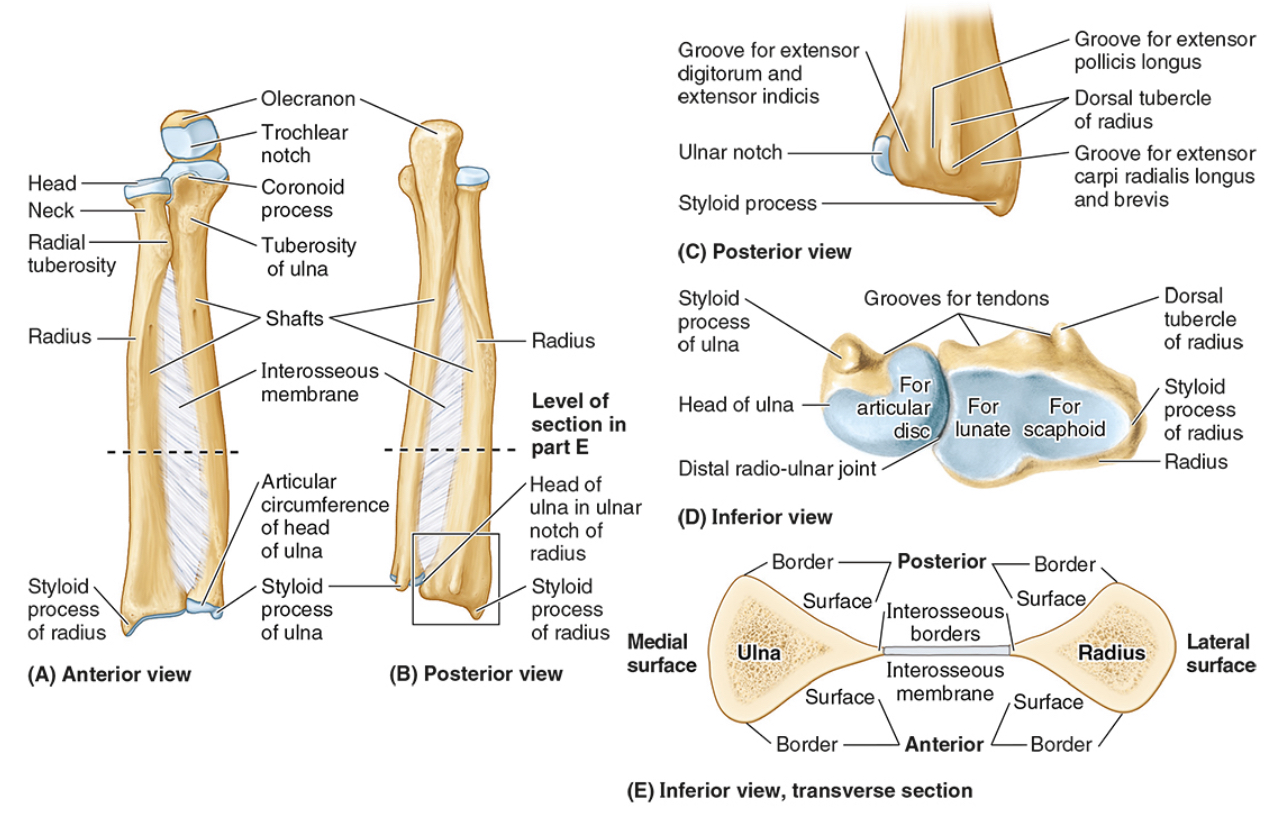

What bones connect to the humerus at the elbow?

The radius and ulna

The ______ connects to the carpal bones of the hand at the wrist joint. The _____ widens distally to provide the proximal articular surface of the wrist (remember, the _____ is on thumb side of the wrist!)

(all the blanks are the same word)

Radius

The head of the radius

The neck of the radius

The radial tuberosity

The ulnar notch

The styloid process

The ____ is the medial forearm bone

Ulna

the olecranon (superior)

The coronoid processes (inferior)

The trochlear notch

The tuberosity of the ulna

The radial notch

The head of the ulna

Distal radio-ulnar joint

What are the three articulations in the elbow joint?

The humerus-ulna articulation

The humerus-radius articulation

The proximal radius-ulnar articulation

The __________ forms a hinge joint, used to flex and extend the forearm

humerus-ulna articulation

The __________ allows the radius to rotate because the concave head of the radius fits onto a round humoral capitulum.

humerus-radius articulation

The __________ is a articulations in the elbow joint that does not directly contribute to motion at the elbow.

proximal radius-ulnar articulation

__________ is palm up to hold your soup bowl

Supination

__________ is palm down to push off the ground

Pronation

When _________ occurs, the radius twists over the front of the ulna.

Pronation

The rounded __________ of the humerus allows the head of the radius to rotate within the radial notch of the ulna

capitulum

Nursemaid’s elbow is a common injury in preschool children, especially girls, caused by sudden pulling of the pronated forearm (e.g., lifting a child). The _________ tear causes subluxation of the radial head.

annular ligament

Nursemaid’s elbow is a common injury in preschool children, especially girls, caused by sudden pulling of the pronated forearm (e.g., lifting a child). The annular ligament tear causes __________ of the radial head.

subluxation

Treatment of nursemaid’s elbow involves?

Treatment involves supination with elbow flexion; healing occurs with sling use for 2 weeks.

The elbow is stabilized by the ulnar and radial collateral ligaments, whereas the _____________ holds the radius against the ulna for rotation.

annular ligament